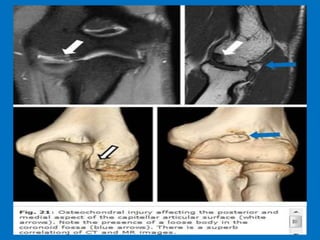

Coronal view: Lateral collateral ligament is completely stripped (yellow arrow).

radial head is subluxed. marrow edema of the coronoid process due to the

fracture (red arrow).

Sagittal view: Radial head is a little bit subluxed posteriorly (yellow arrow).

Large effusion and capsular disruption posteriorly. Contusion of the posterior side

of the capitellum as a result of impaction by the coronoid process (red arrow).